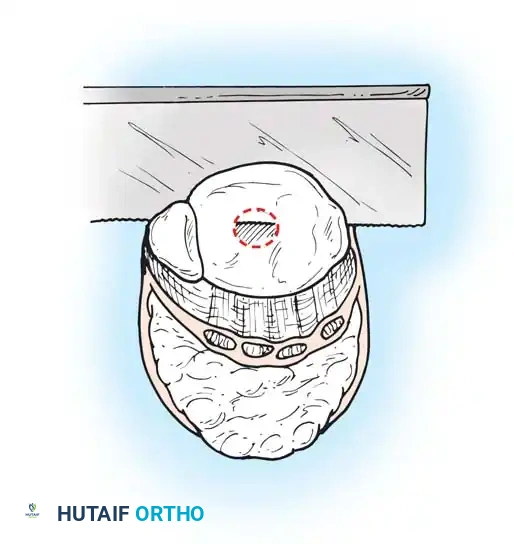

Step 4: Bone Transection

- Retract the heel flap posteriorly. Dissect the soft tissue from the tibia and malleoli.

- Incise the periosteum circumferentially 0.6 cm proximal to the joint line.

- Using an oscillating saw, divide the tibia and fibula at this level. The line of transection must pass just through the dome of the ankle joint centrally.

- Alignment: The plane of the transection must be perfectly parallel to the ground when the patient is standing. Round and smooth all sharp cortical edges with a rasp.